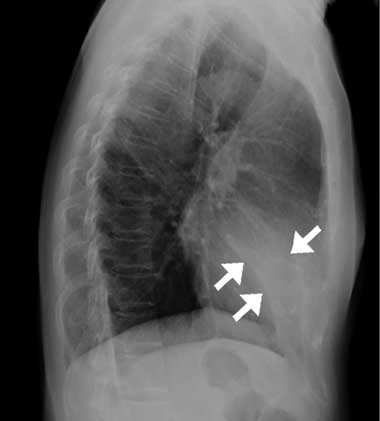

The patient had no prior history of smoking, fever, rhinitis or pharyngitis. Physical examination was unremarkable, except for a rapid respiratory rate (20 breaths/min) and coarse crackles heard during the early inspiratory phase in the middle lung field. A complete blood count, C-reactive protein levels, erythrocyte sedimentation rate, and the results of serum biochemistry were all within normal limits. A chest x-ray revealed a vague opacity in the right lower lung that obliterated the cardiac border in the posteroanterior view, and a wedge-shaped density in the cardiac area in the lateral projection (Box, A). Sputum studies for bacteria, mycobacteria and fungi, and serological tests for Mycoplasma pneumoniae and Legionella pneumophila all gave negative results.